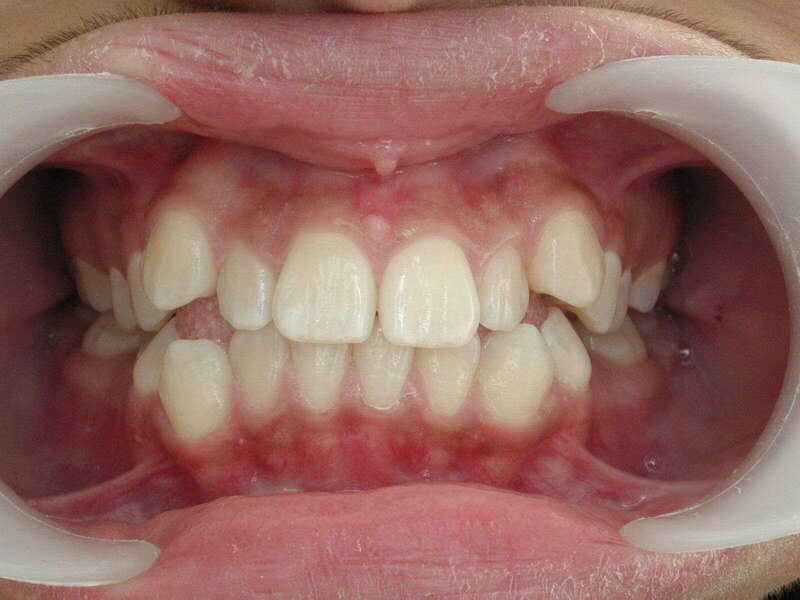

Cas n°1 traité par aligneurs - adolescent

Ce cas d’une adolescente illustre la correction d'une Classe II avec supraclusion par aligneurs. La stratégie thérapeutique a reposé sur une distalisation séquentielle de l'arcade supérieure. Ce mouvement précis a permis de reculer les dents maxillaires étape par étape pour annuler le surplomb (overjet) sans extractions.

Résultats clés :

• Correction fonctionnelle : Retour à un engrènement de Classe I stable et correction du recouvrement vertical.

• Esthétique restaurée : Harmonisation globale du sourire et du profil.

• Approche moderne : Un traitement discret, confortable et hautement prévisible.

Le résultat final montre une occlusion saine et un sourire parfaitement aligné, garantissant une santé dentaire et articulaire optimale pour l'avenir.